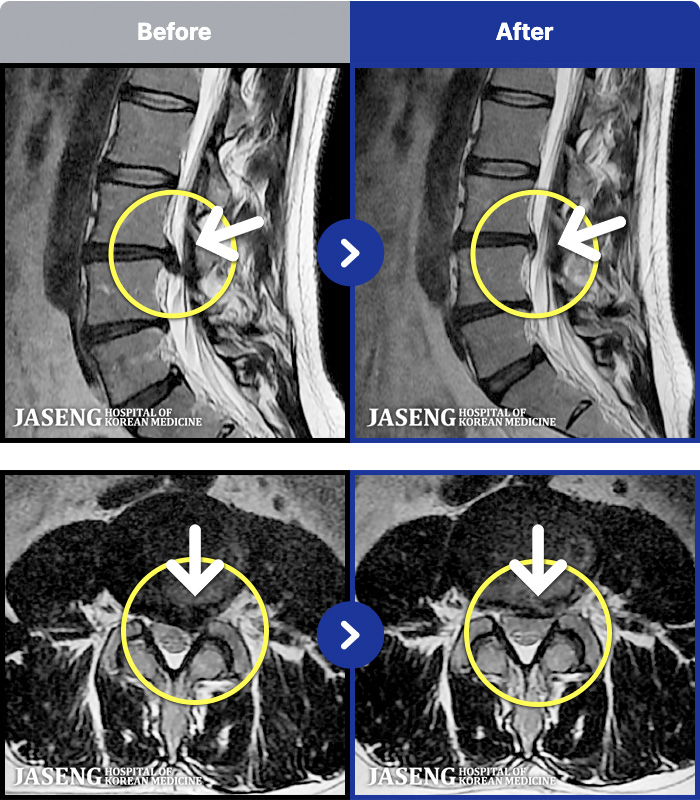

54 MRI ũ ʸ Ȯϼ.